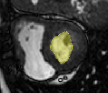

4.3.2 Analysing Heart Function in 4D MRI

Four-dimensional imaging of patient anatomy is gaining interest in the medical community. The temporal analysis of anatomical structures is used to extract the characteristics of related dynamic processes, which often indicate certain pathologies [16, 26, 3]. In this section, we apply nWESD to the shapes of the hearts extracted from four dimensional cardiac images of five different patients. The scan of each patient captures a full cycle of one heartbeat as a series of 20 3D images. Each image shows the left ventricle (LV) at a specific point in the cycle, from which we manually segment the corresponding blood pool. Our reference is the blood pool extracted from the first frame (diastole). We compute the nWESD scores between this reference and all other shapes extracted from the series of images. Here, we do not normalise the eigenvalues with respect to the global scale since size change is an important aspect of the heartbeat dynamics. The graph given in Figure 8 shows the results of these measurements over time across the five patients. The figure also shows some exemplary images and shapes. We observe that the symmetry of the heartbeat along the systolic (as the blood pumps out of the LV pool) and the diastolic phases (as the blood fills in the pool) is well captured with the nWESD score. Furthermore, the end-systolic phase (the time point with the largest distance w.r.t. the reference) is at different time points for different patients, which is to be expected since the different patient scans are not synchronized in time. In summary, WESD well captures the dynamics of the beating heart, which is to be expected given the continuous link between the differences in eigenvalues and the difference in shape (see Section 2).